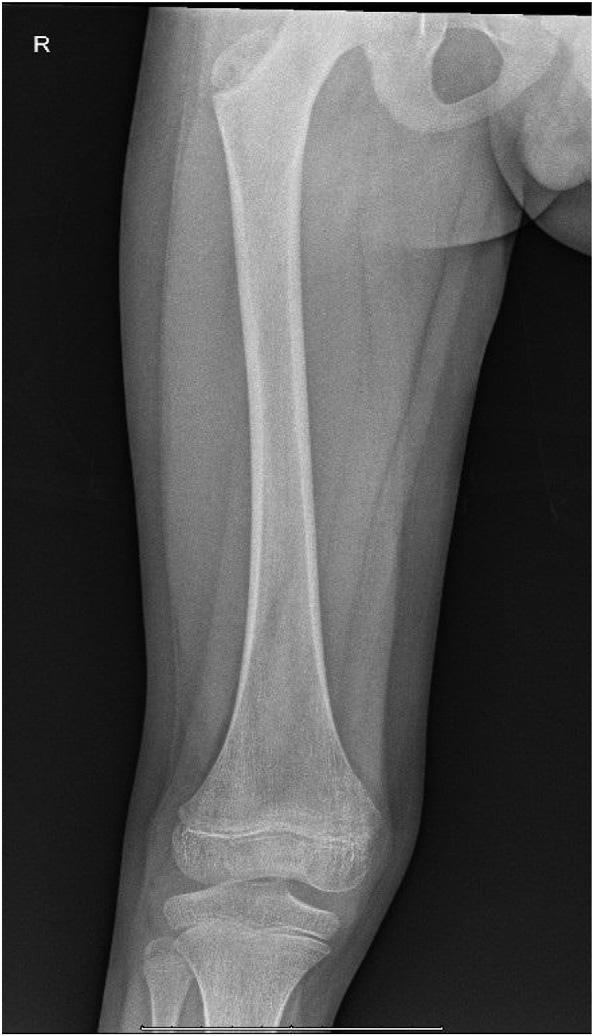

Phone: 1-800-884-2236

222 A Case Report of Delayed Opioid Toxidrome After Administration of Naloxone Maiya Cowan, Prasanna Kumar, Jenny McManus, Sean Bilodeau, Andrew Beck

226 Testicular Traction Technique with Intact Cremasteric Reflex, a Novel Approach for Manual Detorsion: Case Report